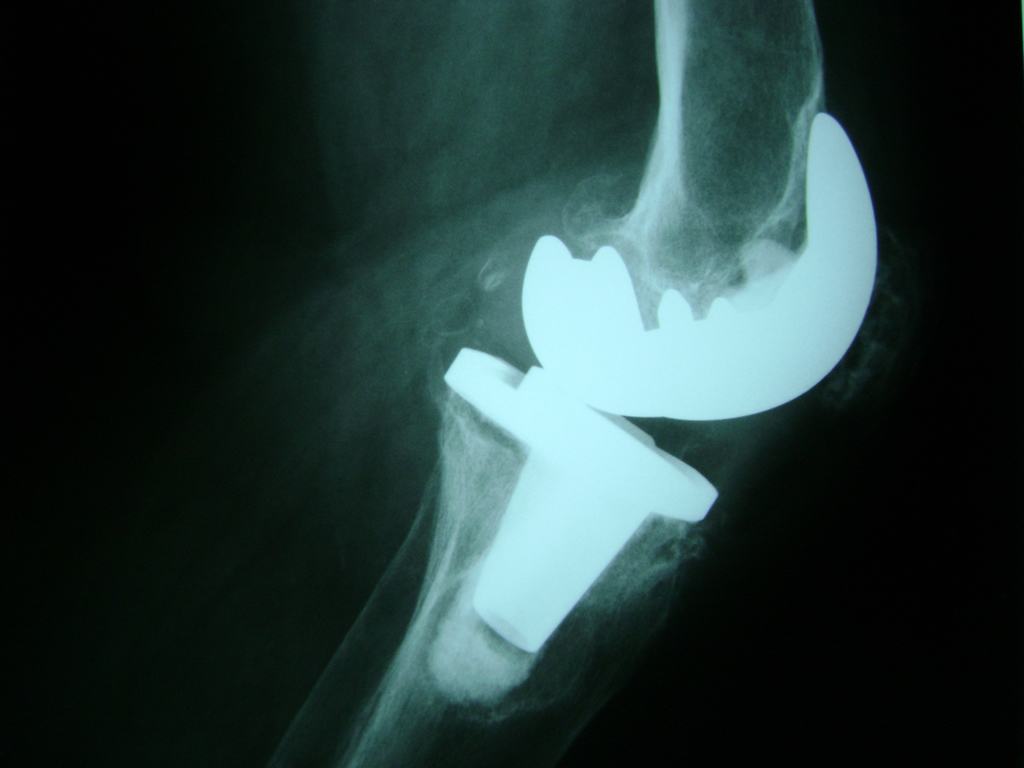

Cirugías de Rodillas